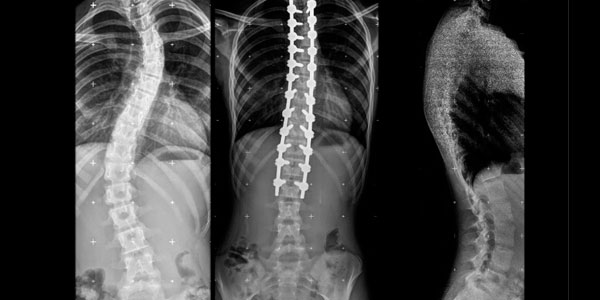

Paciente de 1 año y 8 meses con escoliosis congénita progresiva, se realizo resección de hemivertebra con colocación de tornillos transpediculares.